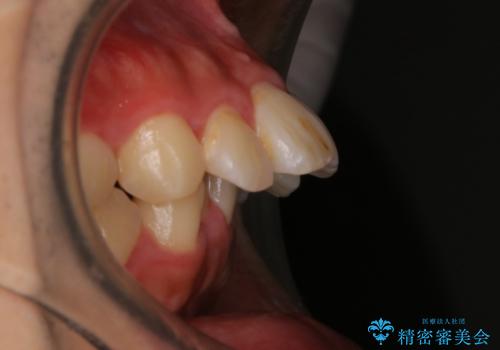

- 上顎前歯の突出感と下顎前歯のガタつきが主訴で来院されました。

出っ歯とガタつきの改善を行うには抜歯が必要と診断し、上下左右第一小臼歯を抜歯する計画を立てました。

抜歯する事で歯の移動量が大きいことからワイヤー表側矯正装置で治療を行うことになりました。